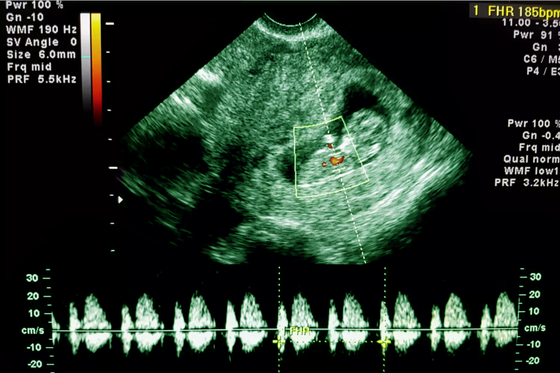

Hogyan hat egy magzatra, ha az anya klasszikus zenét hallgat?

Fontos megállapításokat tett egy, a klasszikus zene és a magzati szívfrekvencia kapcsolatát vizsgáló kutatás: mexikói tudósok arra jutottak, hogy a magzatnak játszott nyugtató zene jótékony hatással lehet a fejlődő szervezetre.